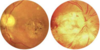

CMV retinitis: symptoms (3)

- floaters

- flashes

- blind spots

Define Pizza Pie retinopathy is caused by ______(virus) and presents with _______(3).

- caused by CMV

- Wool spots

- Infiltrate

- Hemorrhaging

Retinopathies caused by CMV are prevelent in which patient population?

- Immuno-compromised

- Neonates of mothers who are infected

pizza pie retinopathy

(CMV virus)